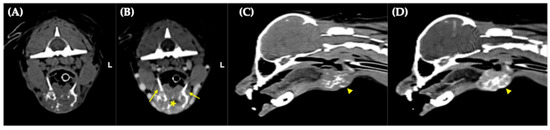

Figure 1

Successful Long-Term Survival Following Thyroid Storm Induced by Radioactive Iodine Therapy in a Dog with Thyroid Carcinoma

An 8-year-old castrated male Pomeranian with a non-resectable functional thyroid carcinoma and concurrent myxomatous mitral valve disease was referred for radioactive-iodine therapy. Due to clinical thyrotoxicosis at referral and concurrent cardiac disease, the radioiodine dose was selected conservatively at the lower end of [...] Read more.

An 8-year-old castrated male Pomeranian with a non-resectable functional thyroid carcinoma and concurrent myxomatous mitral valve disease was referred for radioactive-iodine therapy. Due to clinical thyrotoxicosis at referral and concurrent cardiac disease, the radioiodine dose was selected conservatively at the lower end of the reported therapeutic range. Despite a conservative radioactive iodine dose, the dog developed acute thyrotoxic decompensation consistent with thyroid storm (manifesting as anxiety, diarrhea, hyperthermia, hypersalivation, and marked tachycardia) within hours of treatment. Propranolol and butorphanol administration led to rapid clinical stabilization. Before the second radioactive iodine therapy, methimazole and propranolol were used for subsequent management, effectively controlling thyrotoxicosis risk and enabling a higher radioiodine dose. Serum thyroxine normalized within 1 month after the second treatment, and the dog maintained complete clinical remission thereafter. Radioactive iodine therapy served as definitive therapy to prevent recurrent life-threatening thyrotoxicosis, resulting in a euthyroid state and long-term survival. This case describes the first documented case of a dog with thyroid carcinoma developing probable thyroid storm associated with radioiodine treatment and subsequently achieving a favorable prognosis. Full article